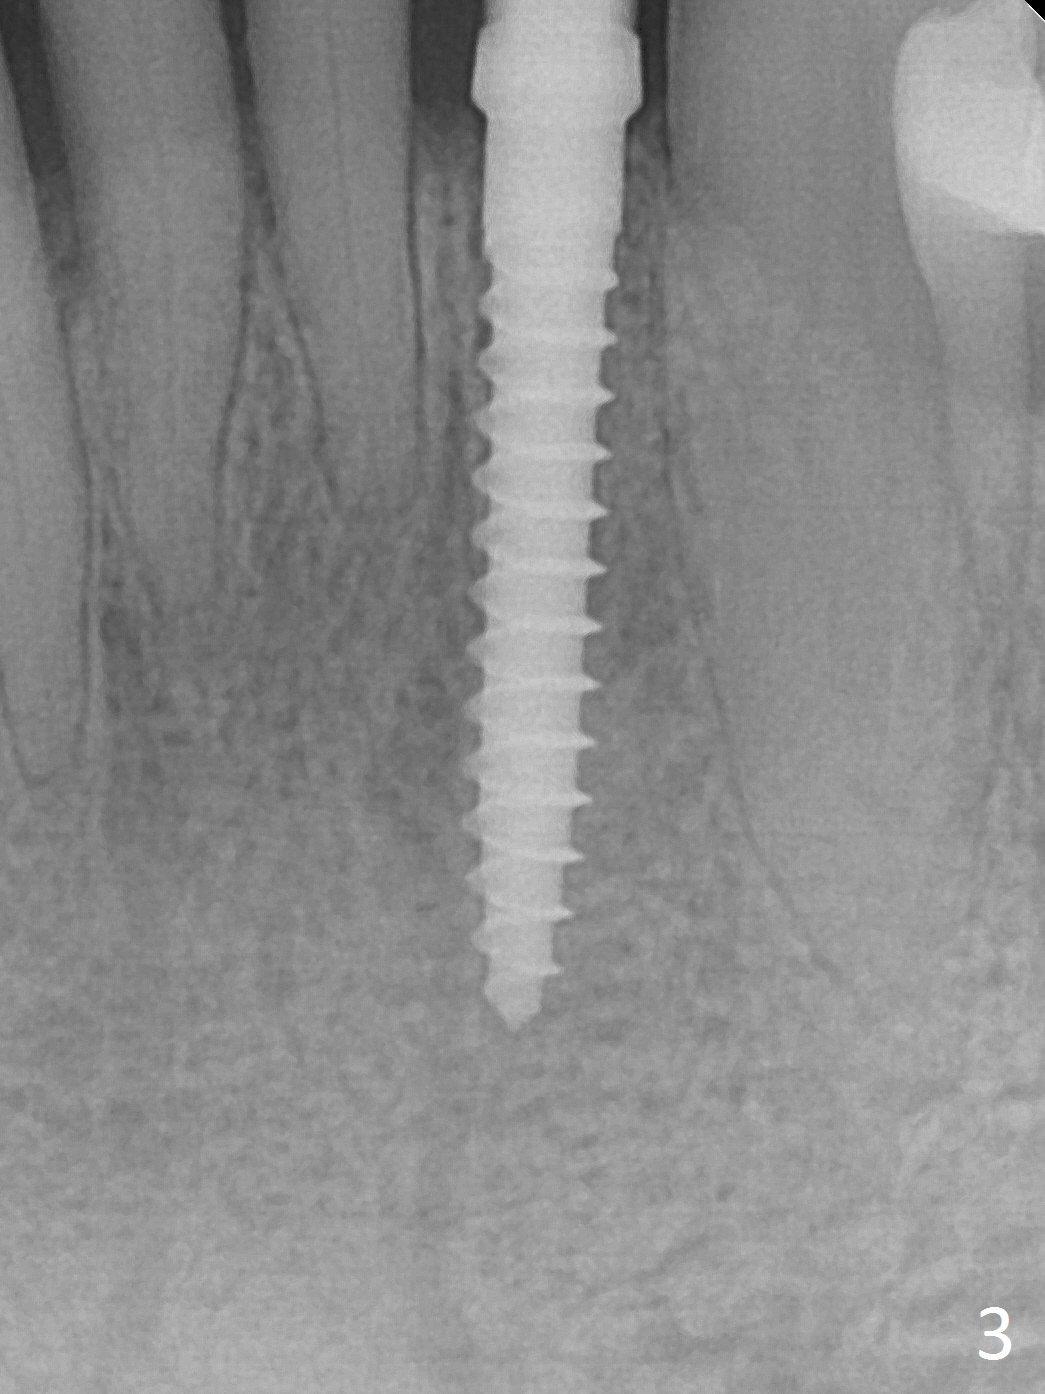

The tooth #23 is going to be extracted because the patient cannot masticate normally with mobility (Fit.1). The gingival depth is measured 2-4 mm after extraction. The 1st intraop PA taken with 1.2 mm drill for 16 mm shows the mesiodistal width is 5.11 mm (Fig.2); a 2.5x14(2) mm 1-piece implant is placed with >35 Ncm (Fig.3 with allograft placed). Following abutment preparation, an immediate provisional is fabricated to close the socket (Fig.4 P). There is no bone loss (Fig.5) or gingival inflammation (Fig.6 after reprep) 3 months postop. The narrow implant (2.5 or 2.0 mm) is indicated in the narrow edentulous space. The distal crest seems to be reduced in density and lower in height 1 year 7 months (Fig.7) and 1 year 11 months (Fig.8) post cementation. The severity does not worsen probably related to use of water pik. The crown looks bulky probably due to too large the abutment and too buccal placement of the implant (Fig.9, 10, as compared to Fig.1). A 2 mm implant may help?